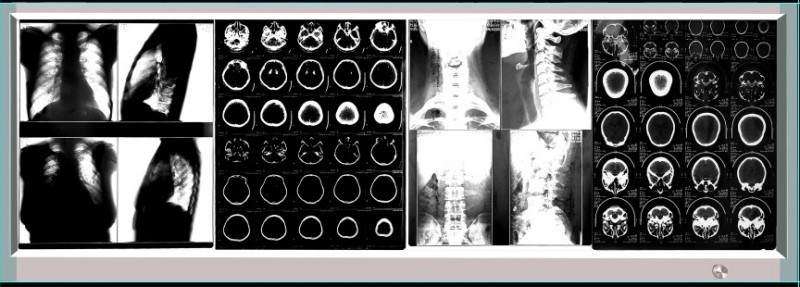

LED单联观片灯 LED双联观片灯 LED三联观片灯 LED四联观片灯

四联LED观片灯 四联LED观察灯 四联LED读片灯 四联LED阅片灯

四联LED观片灯,LED调光插片观片灯